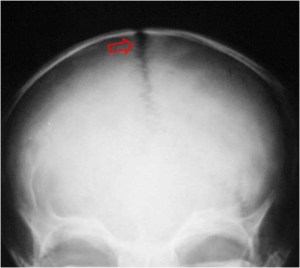

SIGNO DE LA SUTURA ENSANCHADA

Signo de hipertensión intracraneal en la radiografía de cráneo. Consiste en la separación mayor de 2 mm (en niños mayores de 3 años) en la porción interdigitada de la sutura, con más frecuencia la coronal y la sagital (flechas). Puede producirse por hidrocefalia, sangrado, meningitis, encefalitis, tumor cerebral, etc.

Las imágenes corresponden a las radiografías lateral (arriba) y anteroposterior (abajo) de cráneo en un paciente con hipertensión intracraneal secundaria a tumor cerebral.